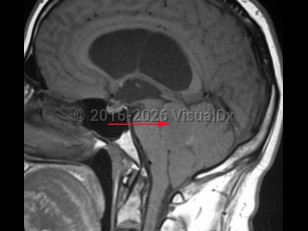

An ependymoma is a tumor of the brain or spinal cord arising from ependymal cells. Ependymomas account for 4% of central nervous system (CNS) tumors in adults and 10% of CNS tumors in children. In children, they are most often located in the 4th ventricle and posterior fossa, whereas in adults, they are more frequently located in the spinal cord. In the spinal cord, they tend to occur centrally, causing symmetric cord expansion. Peak incidence in adults occurs between 30 and 40 years of age.

Signs and symptoms depend on tumor location but may include headache, vomiting, papilledema, lethargy, ataxia, nystagmus, weakness or difficultly walking, sensory disturbance, urinary or bowel dysfunction. Ependymomas have a high incidence in patients with neurofibromatosis type 2.